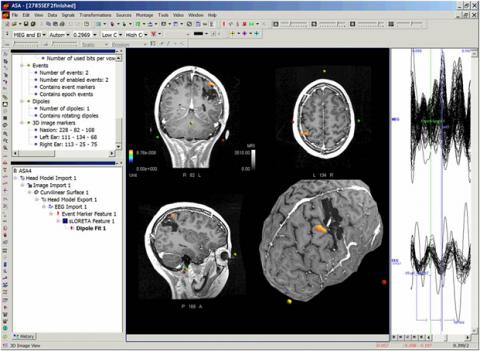

The resulting image below is from the final output of Dr. Bowyer`s data and was used in her presentation. Averaged traces are shown on the rightmost window. In the center window, one can see the dipole fit result visualized in the MRI slices as well as on the curvilinear surface. The dipole was calculated on somatosensory evoked fields (SEF) and localized to the post central gyrus in the anterior margin on the tumor resection.

Dr. Bowyer used a combination of swLORETA and dipole fit for her presentation on MEG source analysis in asa. For Dr. Bowyer, the swLORETA calculated an initial solution, visualized in data-output and in the 3D brain-space. She then automatically fed the maximum of this solution into the dipole fit algorithm. The swLORETA was calculated first in order to prevent the dipole fit algorithm from getting stuck at a local maximum. The a priori information coming from the maximum result of the swLORETA solution not only avoids the unlikely but undesirable pitfall, it also ensures that the dipole fit outputs the highest possible localization accuracy.